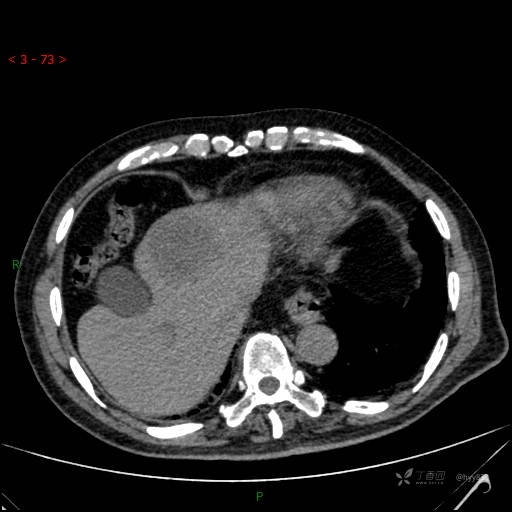

静脉期

img